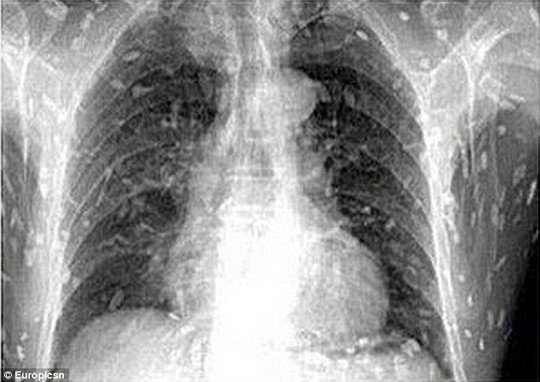

Sán xuất hiện khắp cơ thể người đàn ông

Trước đó, người này đã đến bác sĩ khám và than phiền về việc đau bụng, ngứa da. Kết quả quét toàn bộ cơ thể cho thấy sán dây ký sinh trên khắp cơ thể của bệnh nhân. Người này cho biết trong thời gian dài, anh là tín đồ của món sashimi (cá sống). Do đó, các bác sĩ tin rằng nguyên nhân người đàn ông nhiễm sán là do ăn quá nhiều cá và thịt chưa nấu chín kiểu Nhật.

Sau đó, anh được điều trị tại Bệnh viện Nhân dân số 8 ở Quảng Châu, tỉnh Quảng Đông, Trung Quốc.